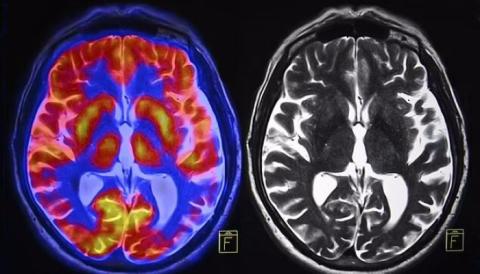

به گزارش سیتنا، دکتر وینود منون، استاد روانپزشکی دانشگاه استنفورد و تیمش، مدلی بر پایه شبکه عصبی عمیق طراحی کردند که می‌تواند با دقت بالای ۹۰ درصد اسکن‌های تصویربرداری تشدید مغناطیسی کارکردی مغز افراد را به دو دسته زن و مرد تفکیک کند.

نتایج نشان داد تفاوت‌هایی در نواحی مغزی مسئول خیال‌پردازی، حافظه و تصمیم‌گیری بین دو جنس وجود دارد.

بیشتر این تفاوت‌ها مربوط به شبکه حالت پیش‌فرض، جسم مخطط و شبکه لیمبیک است که نقش مهمی در فرایندهای ذهنی مانند رویاپردازی، برنامه‌ریزی، تصمیم‌گیری و احساسات دارند.